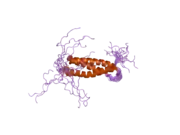

Spartin is a protein that in humans is encoded by the SPG20 gene.[3][4][5]

This gene encodes a protein that contains a MIT (Microtubule Interacting and Trafficking molecule) domain. This protein may be involved in endosomal trafficking, microtubule dynamics, or both functions. Spartin loss has been associated to mitochondrial dysfunction, impaired complex I activity and altered pyruvate metabolism.[6] Frameshift mutations associated with this gene cause autosomal recessive spastic paraplegia 20 (Troyer syndrome).[5] Troyer syndrome (SPG20) is a complicated type of hereditary spastic paraplegias (HSPs).[7] HSP is a category of neurological disorder characterized by spasticity and muscle weakness in the lower limbs.[7]